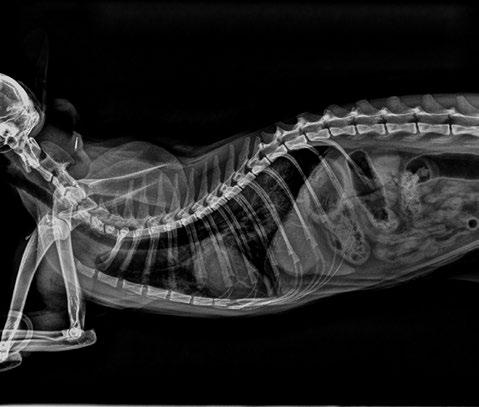

En las vistas laterales, el vertebral heart score (VHS) era de 7,75 vértebras (rango 6,7-8,1). No se observó desplazamiento dorsal de la tráquea, ni mayor apoyo cardiaco sobre las estérnebras teniendo en cuenta la edad del paciente. Se observó un patrón alveolar en zonas caudodorsales al corazón (figura 1), y patrón intersticial difuso generalizado. En la vista dorsoventral, se apreciaba una silueta cardiaca con forma de “corazón de San Valentín”, sugestivo de aumento del AI o bilateral de atrios (figura 2).

Mediante la radiografía torácica, se determina un VHS normal en gatos de 7,5+/- 0,3 (Buchanan 2000). Esta técnica tiene una sensibilidad baja y especificidad elevada (28 % y 95 %, respectivamente) (Soyeon et al. 2023) para la detección de agrandamiento de AI. Esto se refleja en nuestro paciente, con un VHS de 7,75 (normal), pero un aumento considerable de AI ecocardiográficamente.